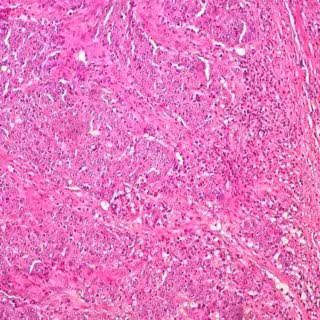

Cáncer de colon

Foto: UCM